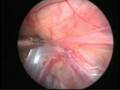

Can this operation done by laparoscopy?

Operation in hernia involves closing of the open passage through which the testis has come down. This can be done from outside as in open surgery or from inside by laparoscopy. If your child has got a hernia on one side, there is a 15 – 25 % chance that he / she may develop a hernia on the opposite side at a later date. With the help of laparoscopy we are able to look at the opposite side to see if the passage is open on that side as well. This can be closed at the same sitting if you wish to. Recovery from surgery, timing of surgery and discharge from hospital are the similar for open surgery and laparoscopic surgery.

However, it is important to note that an open passage does not always mean that your child will get a hernia. There is no harm in opting for a second surgery later if your child at all develops a hernia on the opposite side.

Laparoscopic repairs have a slightly higher chance of recurrence (i.e. the hernia coming back again) as compared to open hernias. You can discuss the pros and cons in details with your doctor when you come for consultation.